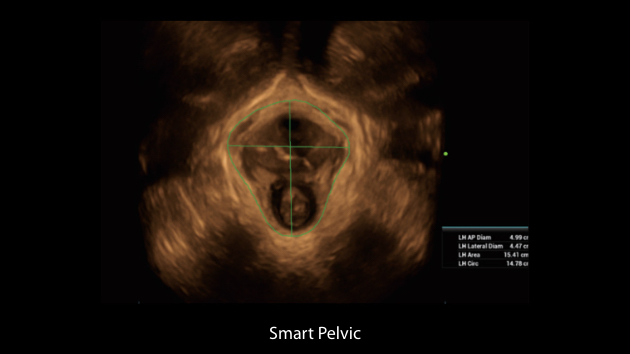

Nuewa I9, kad?nlara ve yenido?anlara y?nelik sa?l?k hizmetleri i?in ?zel olarak tasarlam??t?r ve i?ten d??a yenilik?i bir deneyim sunmaktad?r. Bu yenilikler, karma??k klinik senaryolara ili?kin derinlemesine bilgilere dayal? olarak geli?tirilmi?tir ayr?ca do?ru ve zaman?nda yan?tlar?n yan? s?ra, ola?an├╝st├╝ verimlilik ve ola?an├╝st├╝ kullan?c? deneyimi sunar.